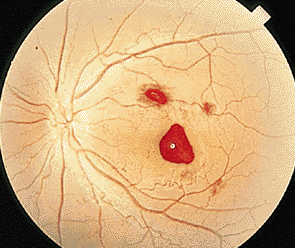

對于很多患者而言,玻璃體變性主要原因就是隨著年齡不斷增加,新陳代謝不斷變緩,使得玻璃體自身變性。比如像星狀玻璃體變性,常常見于50歲以上,不過它只是引起視力的不適,并不會導(dǎo)致視力下降。因為玻璃體內(nèi)新陳代謝緩慢,而出現(xiàn)了含鈣的脂質(zhì)白色小球。而玻璃體變性中更為嚴(yán)重的是出現(xiàn)液化現(xiàn)象,特別是閃輝性玻璃體液化,由于嚴(yán)重眼外傷和手術(shù)后眼內(nèi)出血導(dǎo)致的玻璃體或前房會出現(xiàn)無數(shù)黃白色和其他顏色的膽固醇結(jié)晶。

對于玻璃體混濁這樣復(fù)雜的癥狀,一般的眼科醫(yī)院無法根治,由于眼睛玻璃體的特殊性,目前尚無有玻璃體變性的特效藥,只能經(jīng)過長期的治療和鞏固,使得玻璃體不會出現(xiàn)其他病變。所以對于病情較為嚴(yán)重的玻璃體變性患者而言,就像因為變性引發(fā)的視網(wǎng)膜剝離或玻璃體出血等等,這些會出現(xiàn)視力嚴(yán)重減退,眼睛發(fā)紅、疼痛、畏光等等,一定要到專業(yè)的眼科醫(yī)院進(jìn)行醫(yī)治,比如在廈門眼科醫(yī)院的眼底???,常年來除了眼底病之外,玻璃體變性治療領(lǐng)域在全國也是處于領(lǐng)先位置。